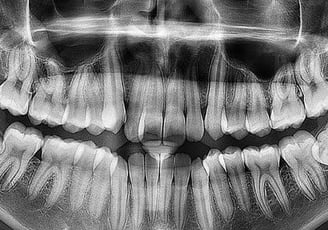

Panoramă dentară

Radiografiile panoramice oferă o imagine completă a întregii cavități bucale, inclusiv a dinților, maxilarelor și articulațiilor temporomandibulare